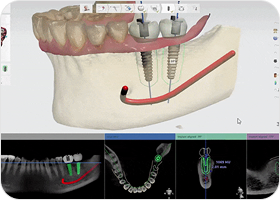

세심한 사전 진단 및 식립 계획

치료 전 3D 디지털 진단을 통한

수술 계획으로 예기치 않은

부작용을 줄일 수 있습니다.

3D 디지털 가이드로 정확하고

빠른 진료가 가능합니다.

저선량 3D CT

저선량 3D CT를 통한 환자의 잇몸뼈 상태,

신경위치를 데이터화하여 정밀한 계획을 수립합니다.

디지털 수술 가이드

잇몸을 절개하는 기존의 방식과 달리,

임플란트 식립 위치에 2mm 정도의 작은 구멍을 뚫어 식립을 진행하여

잇몸 손상과 통증은 줄이고, 빠른 회복이 가능합니다.